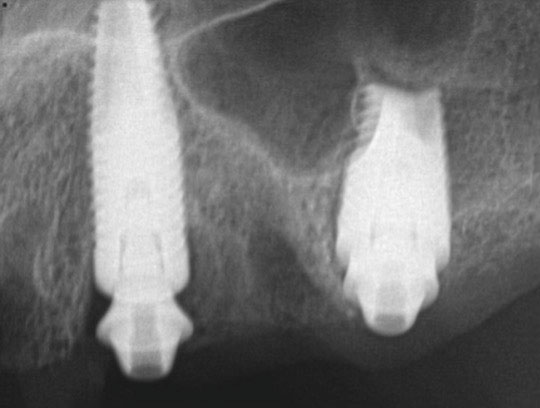

Postoperative x-rays documented the full seating of the prosthesis on the multi-unit abutments (Figure 21 and Figure 22). The patient returned at 1 week postoperatively for a follow-up visit and to review home care. She remarked that the restoration was comfortable and that she was free of discomfort and extremely pleased with the makeover she received in one day.

Fig 22. Postoperative periapical x-rays on the day of surgery demonstrating the provisional restoration with ti-bases fully seated to multi-unit abutments and ideal immediate implant placement.

Figure 22